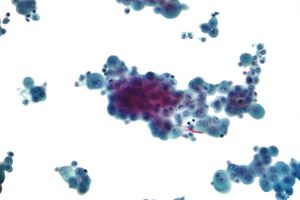

Diagnosing mesothelioma is often difficult because the symptoms are similar to those of a number of other conditions. Diagnosis begins with a review of the patient's medical history. A history of exposure to asbestos may increase clinical suspicion for mesothelioma. A physical examination is performed, followed by chest X-ray and often lung function tests. The X-ray may reveal pleural thickening commonly seen after asbestos exposure and increases suspicion of mesothelioma.[15] A CT (or CAT) scan or an MRI is usually performed. If a large amount of fluid is present, abnormal cells may be detected by cytopathology if this fluid is aspirated with a syringe.[11] For pleural fluid, this is done by thoracentesis or tube thoracostomy (chest tube); for ascites, with paracentesis or ascitic drain; and for pericardial effusion with pericardiocentesis. While absence of malignant cells on cytology does not completely exclude mesothelioma, it makes it much more unlikely, especially if an alternative diagnosis can be made (e.g., tuberculosis, heart failure).[بحاجة لمصدر] However, with primary pericardial mesothelioma, pericardial fluid may not contain malignant cells and a tissue biopsy is more useful in diagnosis.[11] Using conventional cytology diagnosis of malignant mesothelioma is difficult, but immunohistochemistry has greatly enhanced the accuracy of cytology.[بحاجة لمصدر]

Biopsy

Generally, a biopsy is needed to confirm a diagnosis of malignant mesothelioma. A doctor removes a sample of tissue for examination under a microscope by a pathologist. A biopsy may be done in different ways, depending on where the abnormal area is located. If the cancer is in the chest, the doctor may perform a thoracoscopy. In this procedure, the doctor makes a small cut through the chest wall and puts a thin, lighted tube called a thoracoscope into the chest between two ribs. Thoracoscopy allows the doctor to look inside the chest and obtain tissue samples. Alternatively, the cardiothoracic surgeon might directly open the chest (thoracotomy). If the cancer is in the abdomen, the doctor may perform a laparoscopy. To obtain tissue for examination, the doctor makes a small incision in the abdomen and inserts a special instrument into the abdominal cavity. If these procedures do not yield enough tissue, an open surgical procedure may be necessary.[بحاجة لمصدر]

Immunochemistry

Immunohistochemical studies play an important role for the pathologist in differentiating malignant mesothelioma from neoplastic mimics, such as breast or lung cancer that has metastasized to the pleura. There are numerous tests and panels available, but no single test is perfect for distinguishing mesothelioma from carcinoma or even benign versus malignant. The positive markers indicate that mesothelioma is present; if other markers are positive it may indicate another type of cancer, such as breast or lung adenocarcinoma. Calretinin is a particularly important marker in distinguishing mesothelioma from metastatic breast or lung cancer.[12]